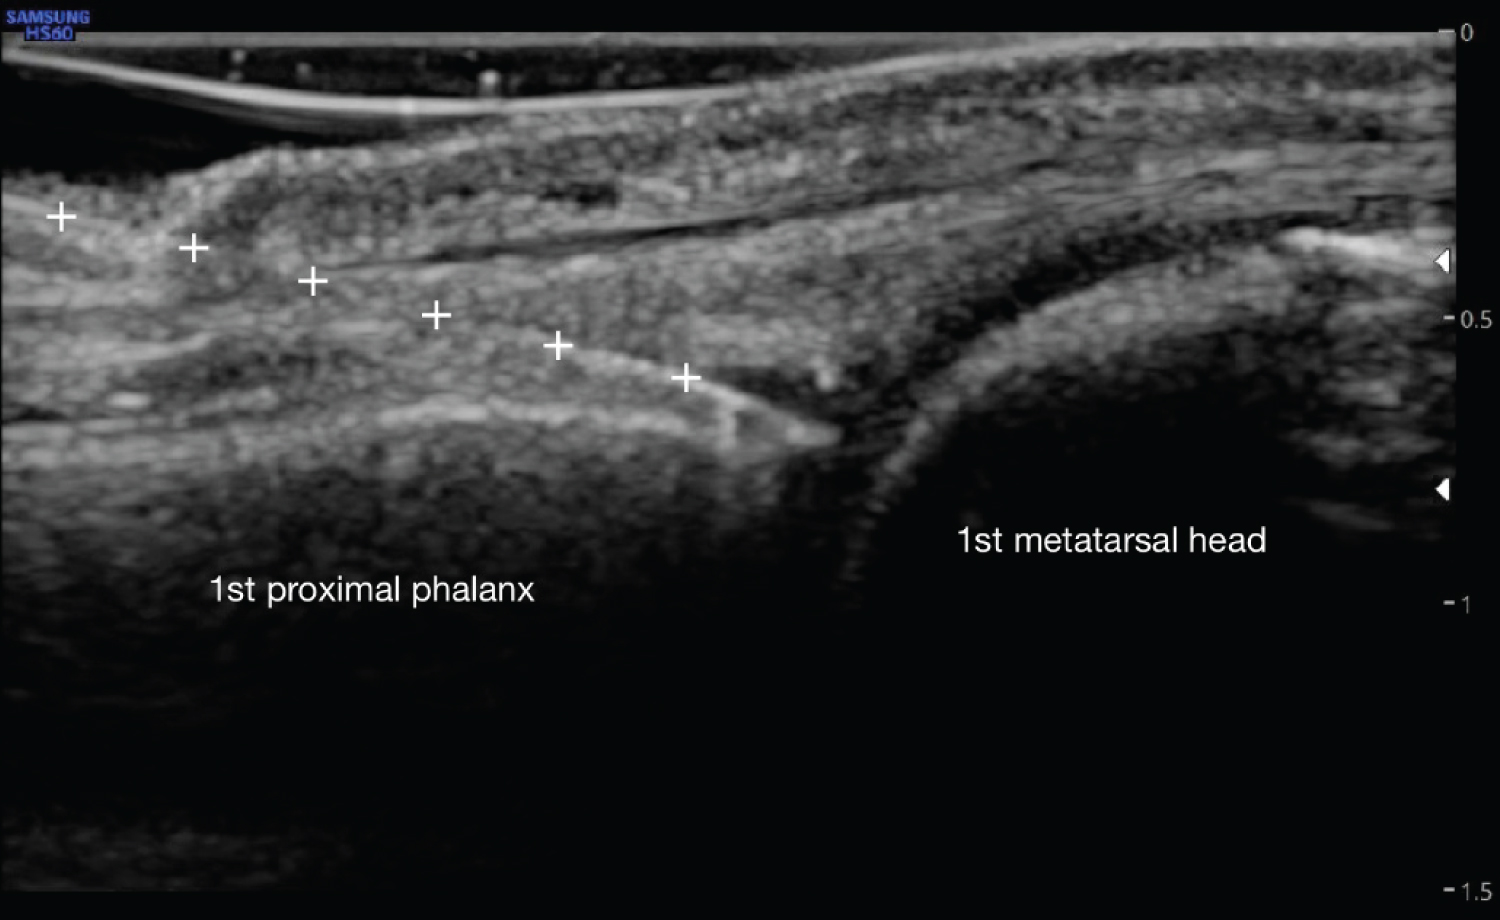

To our knowledge, this study is the first of its kind to investigate the efficacy of PRP for sesamoid fractures. We describe three cases of sesamoid fracture in young adult athletes who received PRP at the first MTP joint via an ultrasound-guided dorsal injection approach (Figure 1).

Figure 1: PRP injection to 1st MTP joint via dorsal in plane approach. White '+' signs indicate needle with tip visualized in the joint space. View Figure 1